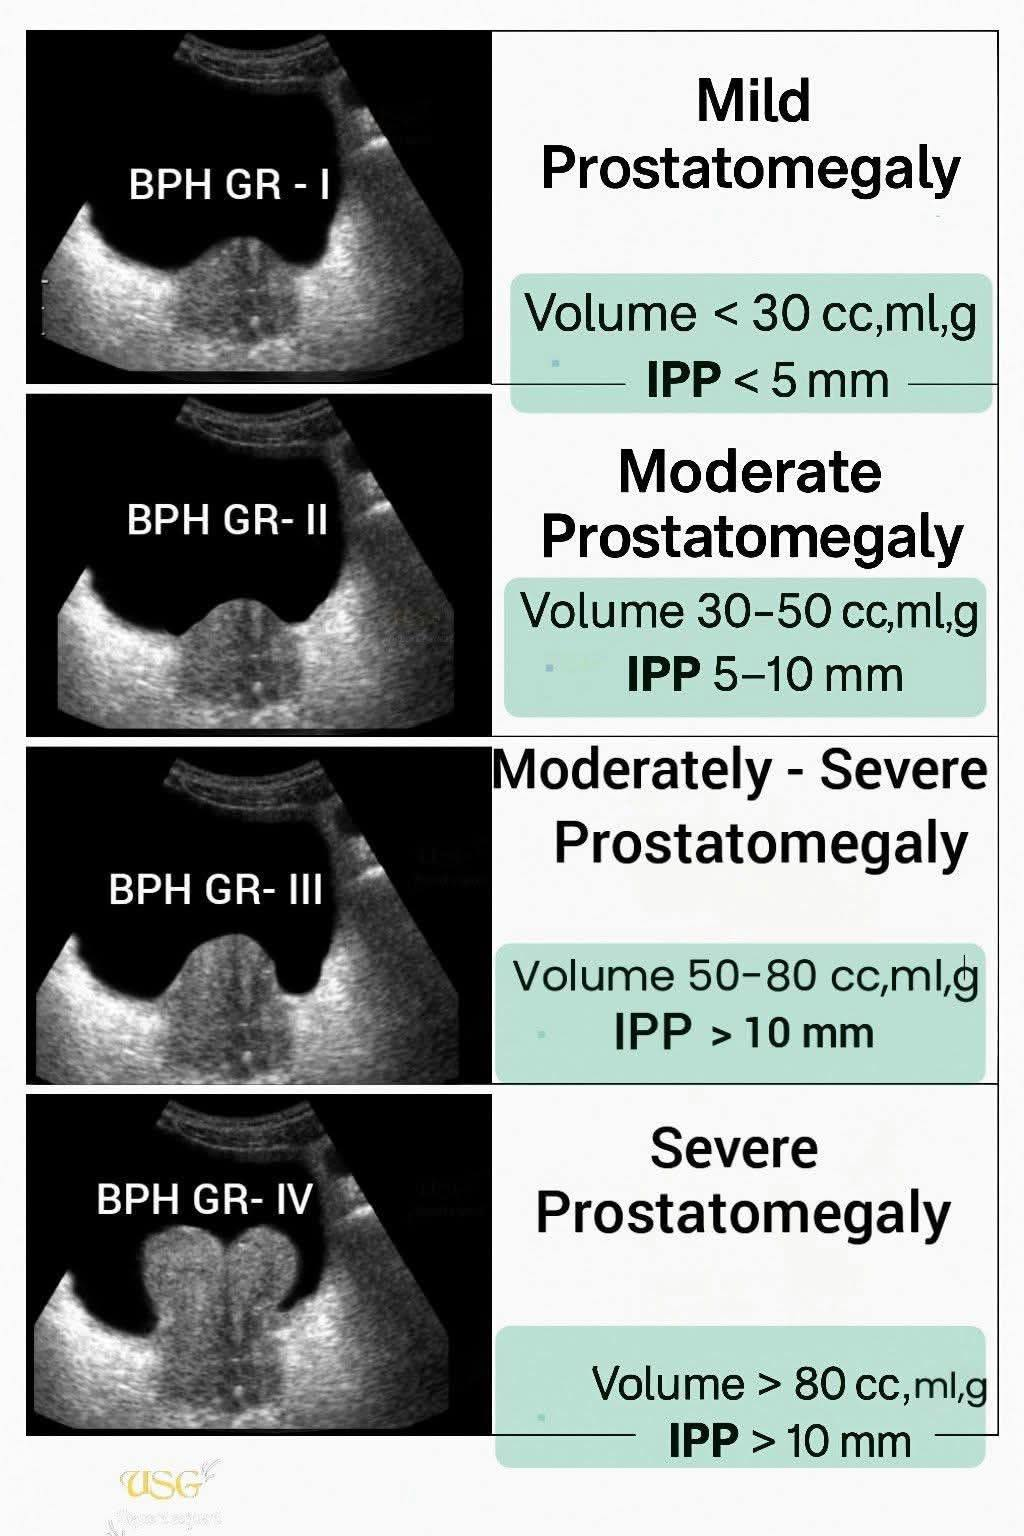

Hình ảnh này cho thấy các mức độ phì đại tuyến tiền liệt (BPH) trên siêu âm dựa trên thể tích tuyến tiền liệt và tình trạng lồi tuyến tiền liệt vào bàng quang (IPP):

1. BPH Độ I – Phì đại tuyến tiền liệt nhẹ

Thể tích: < 30 cc/ml/g

IPP: < 5 mm

2. BPH Độ II – Phì đại tuyến tiền liệt vừa

Thể tích: 30–50 cc/ml/g

IPP: 5–10 mm

3. BPH Độ III – Phì đại tuyến tiền liệt vừa nặng

Thể tích: 50–80 cc/ml/g

IPP: > 10 mm

4. BPH Độ IV – Phì đại tuyến tiền liệt nặng

Thể tích: > 80 cc/ml/g

IPP: > 10 mm

Vì vậy, mức độ nghiêm trọng được xác định bởi cả thể tích tuyến tiền liệt và mức độ lồi vào bàng quang (IPP).